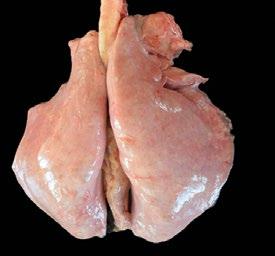

En el matadero se realizó la evaluación postmortem, considerada como la técnica de referencia, midiendo el porcentaje de pulmón afectado y clasificando las lesiones macroscópicas de forma estandarizada en cuatro categorías (Imagen 3).

La severidad y la extensión de la enfermedad, valorada según cada una de las cuatro técnicas (examen físico, auscultación ecografía pulmonar y evaluación post mortem) fue valorada de 0 a 3. A continuación se calculó la sensibilidad y la correlación entre las técnicas, teniendo a la evaluación macroscópica post mortem como referencia.

Imagen 3. Lesión pulmonar delimitada para su cuantificación.

El examen físico es una herramienta valiosa para el cribado inicial y la toma de decisiones en campo, pero puede no detectar los casos más leves o incipientes por no detectar casos subclínicos (un 24,3% de los animales que no presentaban signos clínicos mostraban alteraciones ecográficas compatibles con enfermedad respiratoria).

Además, no tiene la sensibilidad suficiente para clasificar los casos según su gravedad.

La ultrasonografía pulmonar permitió una evaluación objetiva, no invasiva y repetible de las lesiones pulmonares, con capacidad para identificar consolidaciones, líneas B, derrames y abscesos, incluso en animales sin síntomas clínicos.

Aunque presenta limitaciones en lesiones profundas o mediastínicas, su aplicación en corderos en fase de cebo resulta especialmente útil, dada la localización superficial y la localización típica de las neumonías en regiones craneoventrales del tórax. Además, puede servir para monitorizar la respuesta al tratamiento y para implementar estrategias preventivas basadas en el manejo o vacunación.

En conclusión, este estudio demuestra que la ecografía pulmonar es una herramienta fiable, práctica y complementaria para el diagnóstico del complejo respiratorio ovino.

Su uso en condiciones de campo permitiría mejorar el manejo sanitario, reducir el uso innecesario de antibióticos, y avanzar hacia una producción más sostenible y respetuosa con el bienestar animal.

Se recomienda su incorporación a protocolos diagnósticos rutinarios, así como la realización de estudios futuros para relacionar los patrones ecográficos con agentes etiológicos específicos.